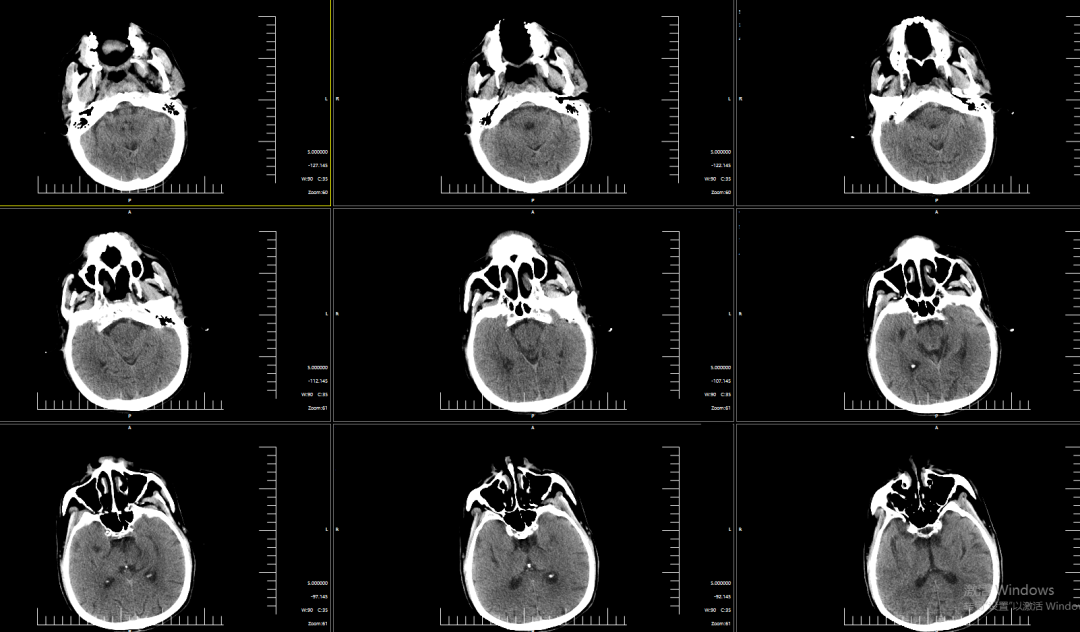

术前影像学检查结果

NCT提示双侧基底节区腔隙性脑梗塞。

DWI提示右侧岛叶、右侧额顶叶明显弥散受限。